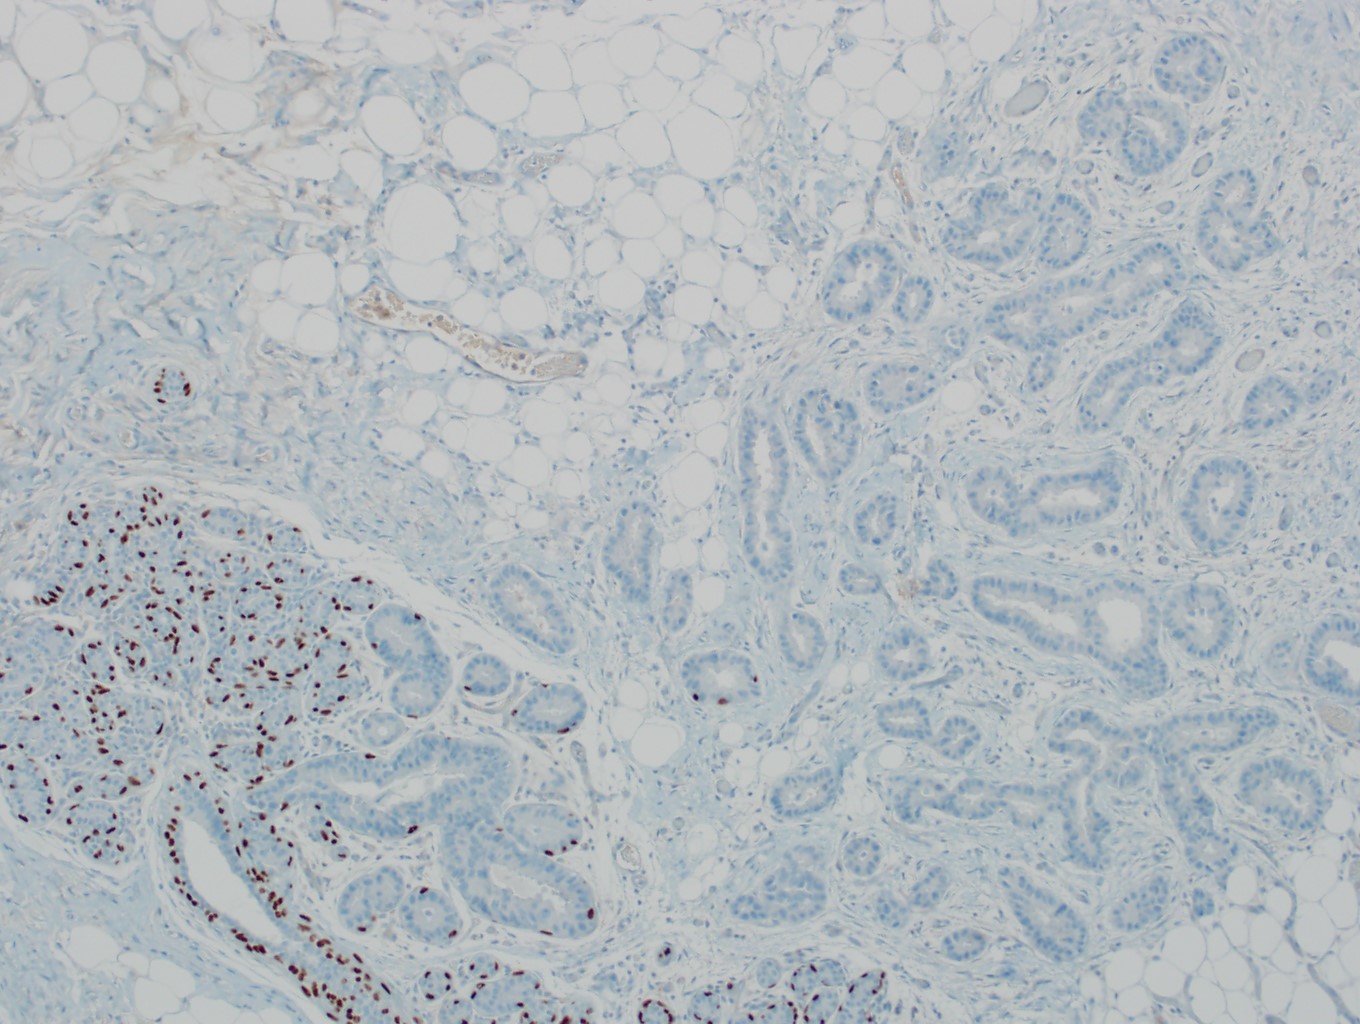

- No myoepithelial cell lining (as seen in DCIS or benign lesions)

Microscopic (histologic) images

Contributed by Julie M. Jorns, M.D., Kristen E. Muller, D.O., Gary Tozbikian, M.D. and Emad Rakha, M.D.

Negative stains

- CK20, CD34

- Myoepithelial markers: p63 (positive in benign lesions), CD10, calponin (Am J Surg Pathol 2001;25:1054, Mod Pathol 2002;15:397)

- Ductal carcinoma in situ involving sclerosing lesions (e.g., sclerosing adenosis):

- IHC using myoepithelial markers shows retained myoepithelial cell layer

A. Calponin and p63. The use of myoepithelial markers is most useful for distinguishing in situ from invasive carcinoma. Utilization of 2 myoepithelial markers, including both a cytoplasmic marker (e.g., calponin or smooth muscle myosin) and a nuclear marker (p63 or p40) is recommended, as myoepithelial expression can be patchy or attenuated (p63 / p40) and show nonspecific expression in endothelial cells (SMMS); the combination of 2 markers provides increased sensitivity and specificity. Both DCIS and invasive breast carcinoma (NST) may show expression of hormone receptors, HER2 and cytokeratins.